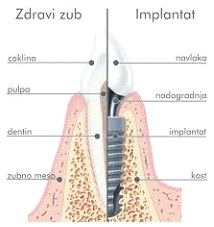

Zubni implanti ili implantati su cilindrični šrafovi koji se ugrađuju u kost vilice i koriste se kao zamena za prirodni koren zuba. Izrađuju se od titanijuma. Zajedno sa nadgradnjom i protetskom krunom zuba čine jedinstvenu celinu za funkcionalnu i estetsku rehabilitaciju jednog ili više zuba koji nedostaju. Kod same ugradnje implanta cilj je ostvariti kontakt spoljašnje površine implanta i okolnog koštanog tkiva kako bi srasli zajedno (pojava se naziva “osteointegracija“) i tako osigurali trajnost zubne nadoknade.

- Implantati se hirurški ugrađuju u kost. Postupak je brzo gotov i bezbolan, budući da se izvodi pod lokalnom anestezijom. Nakon ugradnje implant srasta sa kosti - “osteointegracija“ , što obično traje 2 do 6 meseci.

- Nakon ovog perioda na implant se postavlja nadgradnja (suprastruktura) na koju ide protetska krunica ili neko drugo protetsko resenje u zavisnosti od plana terapija.